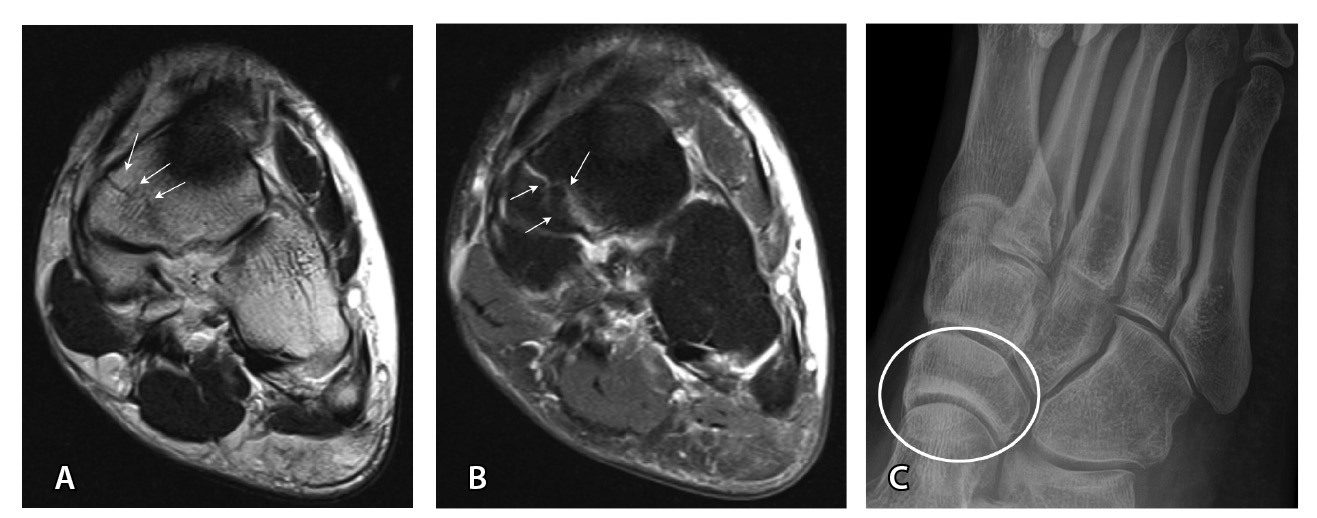

По данным N. El-Liethy и H. Kamal чувствительность сонографии в диагностике повреждения ахиллова сухожилия и сухожилия задней большеберцовой мышцы составила 100%, при этом в последующем результаты подтвердились при помощи МРТ. Существует мнение, что с помощью УЗИ удается классифицировать повреждения ахиллова сухожилия (рис. 6) аналогично МРТ в отношении тендинопатии, частичного повреждения и полного разрыва [58].

Рис. 6. Ультразвуковая диагностика голеностопного сустава: А – неполнослойный разрыв ахиллова сухожилия в области мышечно-сухожильного перехода (стрелки); Б – дефект 90% волокон, заполнен геморрагическим содержимым (пунктирные стрелки). Диастаз волокон, гематома